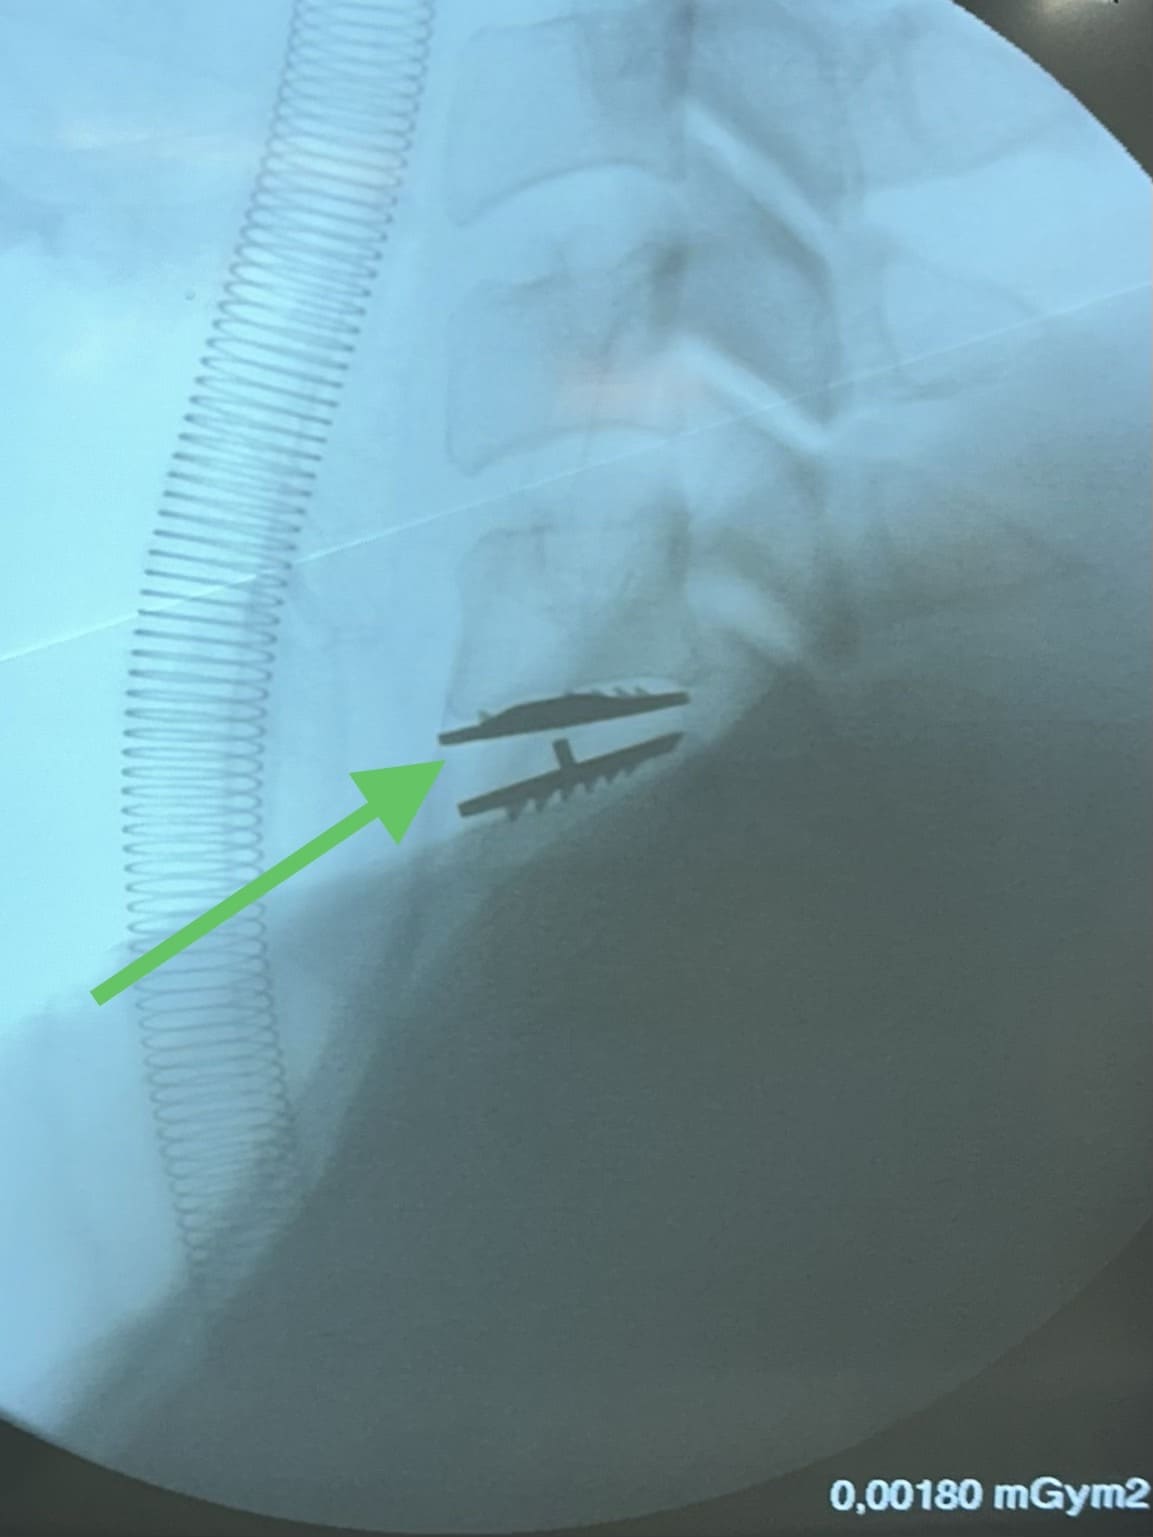

As duas principais técnicas cirúrgicas para hérnia de disco cervical são:

A artrodese cervical é um procedimento cirúrgico que envolve a fusão de duas ou mais vértebras da coluna cervical. A fusão é realizada usando parafusos, pinos ou placas.

A artrodese cervical é indicada para casos de hérnia de disco cervical que não responderam ao tratamento conservador ou que causam dor significativa.

Existem várias técnicas cirúrgicas, o procedimento específico depende da condição do paciente. O Dr. remove discos ou ossos danificados e pode fundir as vértebras afetadas para estabilizar a coluna.